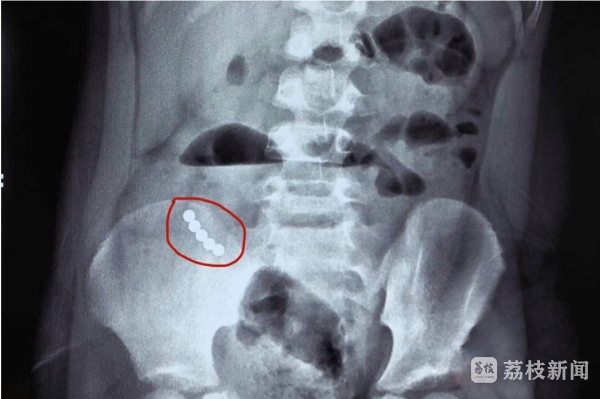

说到“坑娃利器”,磁力珠一定榜上有。关于“儿童误食磁力珠”的危害早就有了铺天盖地的报道。10月22日记者获悉,淮安市妇幼保健院小儿外科的医生从5岁男童小乐腹中取出5颗磁力珠,并将孩子肠道被磨破的4处“破洞”修补完整。

急诊医生做了初步处理后,把孩子收治入院进一步检查发现,小乐的情况必须立即手术。术中探查发现,不同的肠管因为磁力珠粘在一起,导致肠梗阻,肠壁因为缺血坏死之后穿孔,医生取出5颗磁力珠,并将发现的四处穿孔逐一精心修补。医生提醒,磁力珠吸力较强,颜色多彩,小朋友一旦当“糖豆”误食,珠子随着小肠蠕动向下运动,磁力珠相互吸引导致肠梗阻。